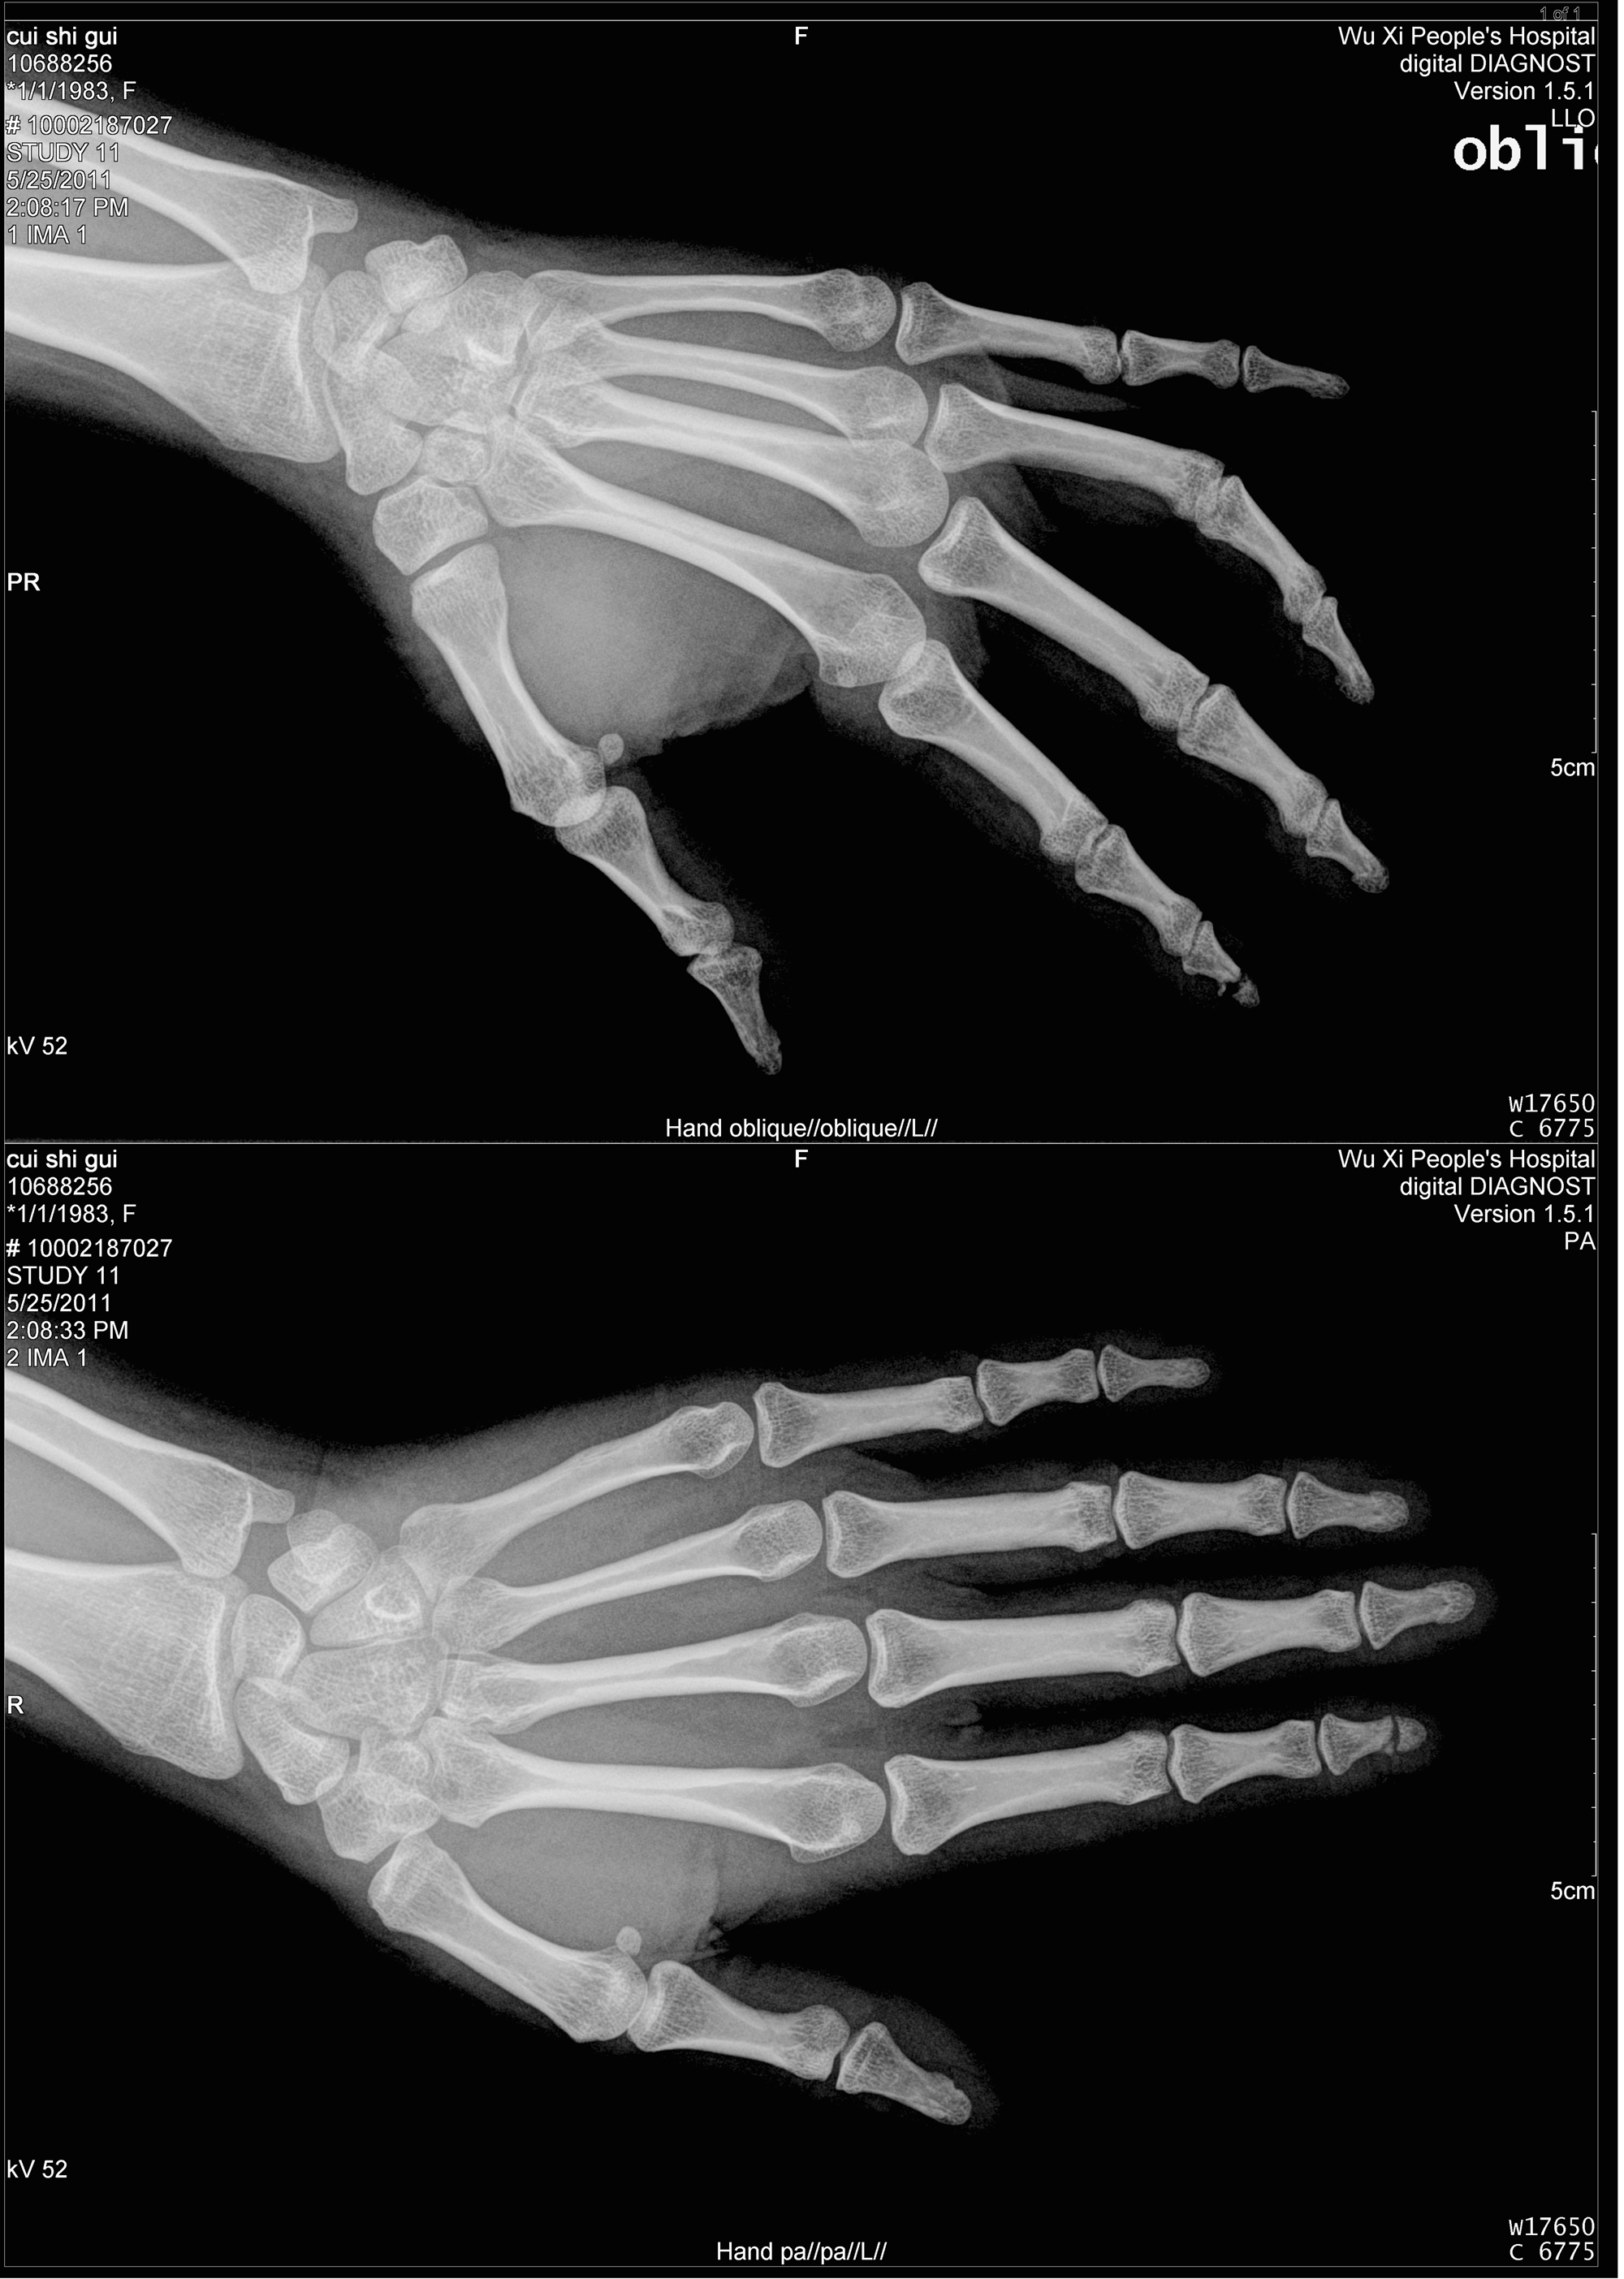

显然,这种改变显示内容的方式将不可避免地导致图片“失真”。这样,医学图像显示的基本要求也发生了变化。因此,仅就分辨率而言,不仅必须选择医疗显示器,而且还必须根据不同的系统选择不同的分辨率。监视器的分辨率与图像本身的分辨率密切相关。 Appropriate selection of the resolution of the monitor can effectively reduce the purchase cost of the monitor.普通图像的分辨率如下:心血管血管造影术,数字胃肠机:1024X1024(单幅图像),菜单为1280X1024 MRI:256X256或512X512(单幅图像)CT:512X512或1024X1024(单幅图像)DR / CR:DSA超过500万(单幅图像) ,CT,MRI换句话说,只需要一个1280X1024分辨率的监视器即可显示单个图像。但是,如果要查看多个图像,例如CT 3X4或4X5的多个图像,则分辨率为1536X2048和2048X256 0.。高分辨率显示器,例如三或五百万像素的显示器。 DR和CR图像的分辨率通常超过500万像素,最好使用3或500万像素的显示器。以上配置选项适用于放射科医生进行图像诊断,一般的临床观察结果可能是合适的。将分辨率降低到100万像素或200万像素以节省成本。